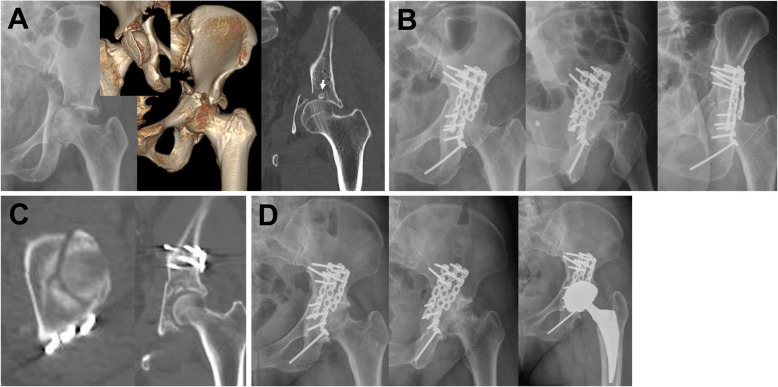

Fig. 3.

A 47-year old woman involved in a traffic accident. a Immediate radiograph and three-dimensional computed tomography (CT) images show transverse and posterior wall fractures of acetabulum. Dome impaction (arrow) was observed in coronal view of CT scan. b Postoperative radiographs revealed that satisfactory reduction and fixation were achieved. c However, axial and coronal CT views show a residual gap > 3 mm and poor reduction and fixation of the dome fragment. d Osteoarthritis developed and total hip arthroplasty was performed at 6 months after surgery